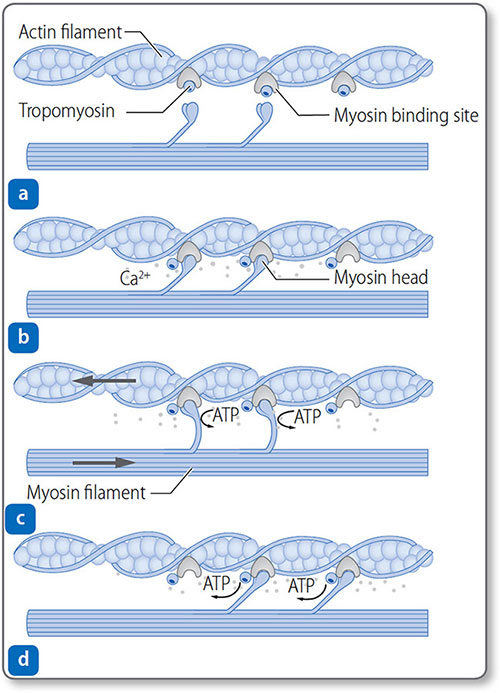

Myofibril contraction

Thin filaments consist of actin, tropomyosin and troponin complexes (Figure 1.27).

- Troponin T attaches each troponin complex to the tropomyosin

- Troponin I inhibits the binding of myosin heads to actin

- Troponin C binds to Ca2+.

The binding of Ca2+ to troponin C exposes the myosin-binding site, allowing actin−myosin cross-bridges to form.

Figure 1.27: Mechanism of myocardial contraction. (a) Myosin-binding sites on actin filaments are blocked by tropomyosin. Ca2+ released after depolarization binds to troponin. (b) Troponin changes conformation, exposing the binding site. Myosin heads bind actin. (c) Power stroke occurs as myosin heads pull filaments and shorten the sarcomere. (d) Myosin heads reset and can rebind.

The sliding filament model of contraction The myosin ‘power stroke’ pulls the filaments so that they slide in opposite directions; this sliding shortens the sarcomere and in turn contracts the myocardium. Cycles of myosin-head binding to actin, contracting, disconnecting and then reattaching – a ‘ratcheting’ effect – progressively shorten the sarcomere as long as intracellular Ca2+ remains high. Both contraction and relaxation are energy dependent 39(ATP consuming). In the heart this is a continual cycle hence the large concentration of mitochondria and glycogen stores.